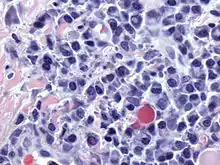

![]() Micrograph of malignant plasma cells (plasmacytoma), many displaying characteristic "clockface nuclei", also seen in normal plasma cells. H&E stain. | |

Plasma cells are large lymphocytes with abundant cytoplasm and a characteristic appearance on light microscopy. They have basophilic cytoplasm and an eccentric nucleus with heterochromatin in a characteristic cartwheel or clock face arrangement. Their cytoplasm also contains a pale zone that on electron microscopy contains an extensive Golgi apparatus and centrioles . Abundant rough endoplasmic reticulum combined with a well-developed Golgi apparatus makes plasma cells well-suited for secreting immunoglobulins.[4] Other organelles in a plasma cell include ribosomes, lysosomes, mitochondria, and the plasma membrane.

Plasmacytoma, multiple myeloma, Waldenström macroglobulinemia, heavy chain disease, and plasma cell leukemia are cancers of the plasma cells.[33] Multiple myeloma is frequently identified because malignant plasma cells continue producing an antibody, which can be detected as a paraprotein. Monoclonal gammopathy of undetermined significance (MGUS) is a plasma cell dyscrasia characterized by the secretion of a myeloma protein into the blood and may lead to multiple myeloma.[34]